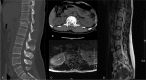

Patient concerns: A 46-year-old Chinese woman suffered from severe lower back pain with grade 0 muscle strength of lower limbs, without any sensory function below the injury level, with an inability to urinate or defecate after a motor vehicle accident. Imaging studies confirmed that she had Magerl type A 3.2 L1 burst fracture.

Diagnoses: Burst fracture at L1.

Interventions: The patient underwent PPSF at the level of T12 to L2, but her neurological function did not fully recover after the operation. One week after the injury, we performed TESCD on her.